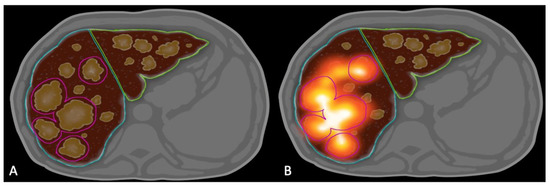

At the time of treatment, Y90 SPECT/CT was obtained immediately following radioembolization for each patient. MIM Sureplan® software v.6.9 (MIM Software, Cleveland, OH, USA) was used retrospectively to create a volumetric region of interest around the 5 largest tumors in each treated lobe using the semi-automated dosimetry module of the software. Contours around tumors and normal liver were created on the most recent contrast enhanced cross-sectional imaging (CT or MRI) before Y90 therapy (Figure 8). They were then fused to Y90 SPECT/CT images using MIM software. The dose to the cumulative tumor and NTL were then calculated manually and using the software-generated dose volume histograms (DVH). Mean NTL was calculated for each treated lobe. If a patient had bilobar treatment, an average of mean NTL for the 2 therapies were used for the analysis.

Figure 8.

Dosimetry Method Diagram. (A) contour the target lobe and 5 largest tumors on the target lobe. (B) Bremsstrahlung SPECT/CT showing the cumulative activity in the 5 and 5 largest tumors in the target lobe.